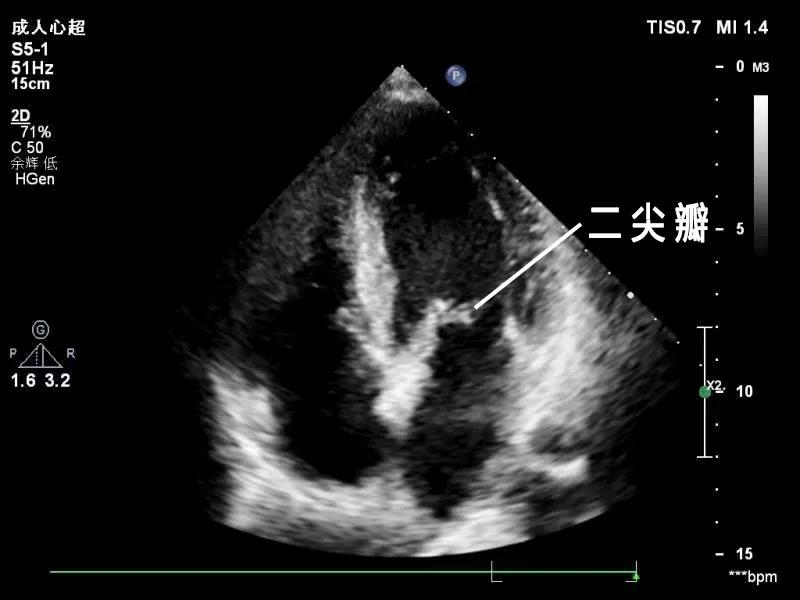

心脏超声是利用超声波的原理判断心脏的结构和血流方向是否存在异常。心脏超声是目前唯一的、无创的、无辐射,并实时显示心脏结果的检查方法。

心脏超声最常用的方式是经胸超声心动图检查,对于有些肥胖、肺气肿、胸廓畸形患者,如果经胸超声检查的图像质量不理想而影响对病情的判断时可以采取经食道超声检查。

心脏超声主要是观察心脏的结构和功能,比如先天性心脏病、瓣膜病是完全可以通过心脏超声来确诊和排除的,其他如冠心病、高血压心脏病、心肌病、心律失常等心脏病,心脏超声只能提供心脏结构及功能的信息,不能仅仅依靠心脏超声来确诊或排除心脏病,还需要其他方法来综合判断。